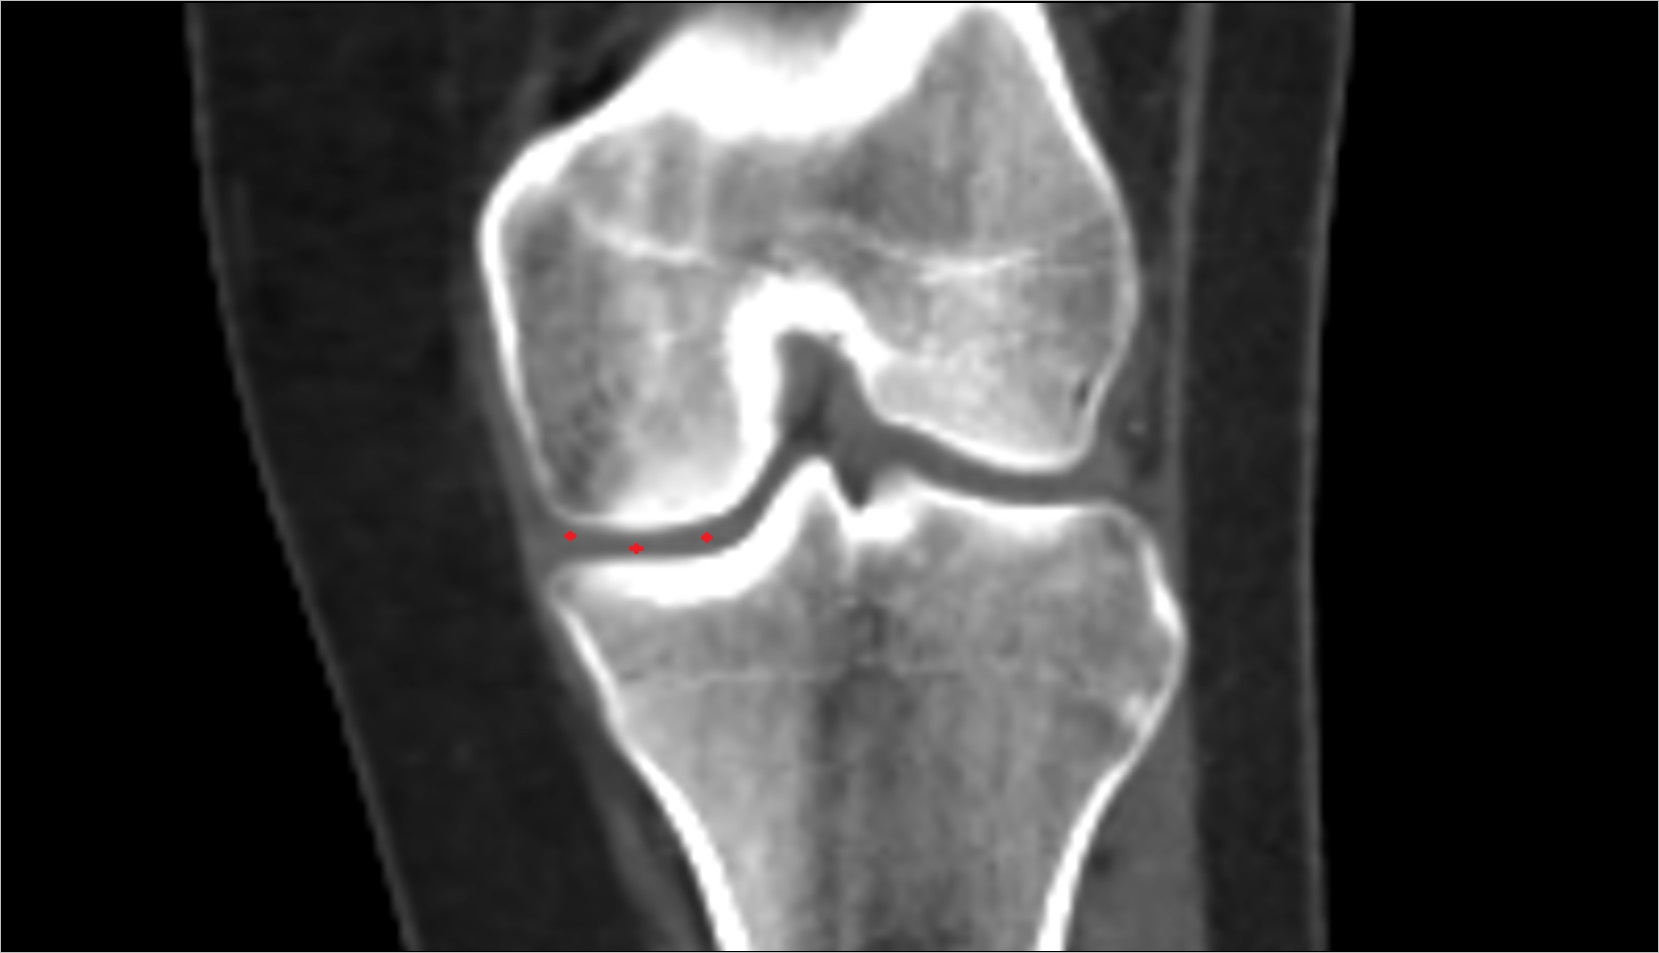

- Knee Joint